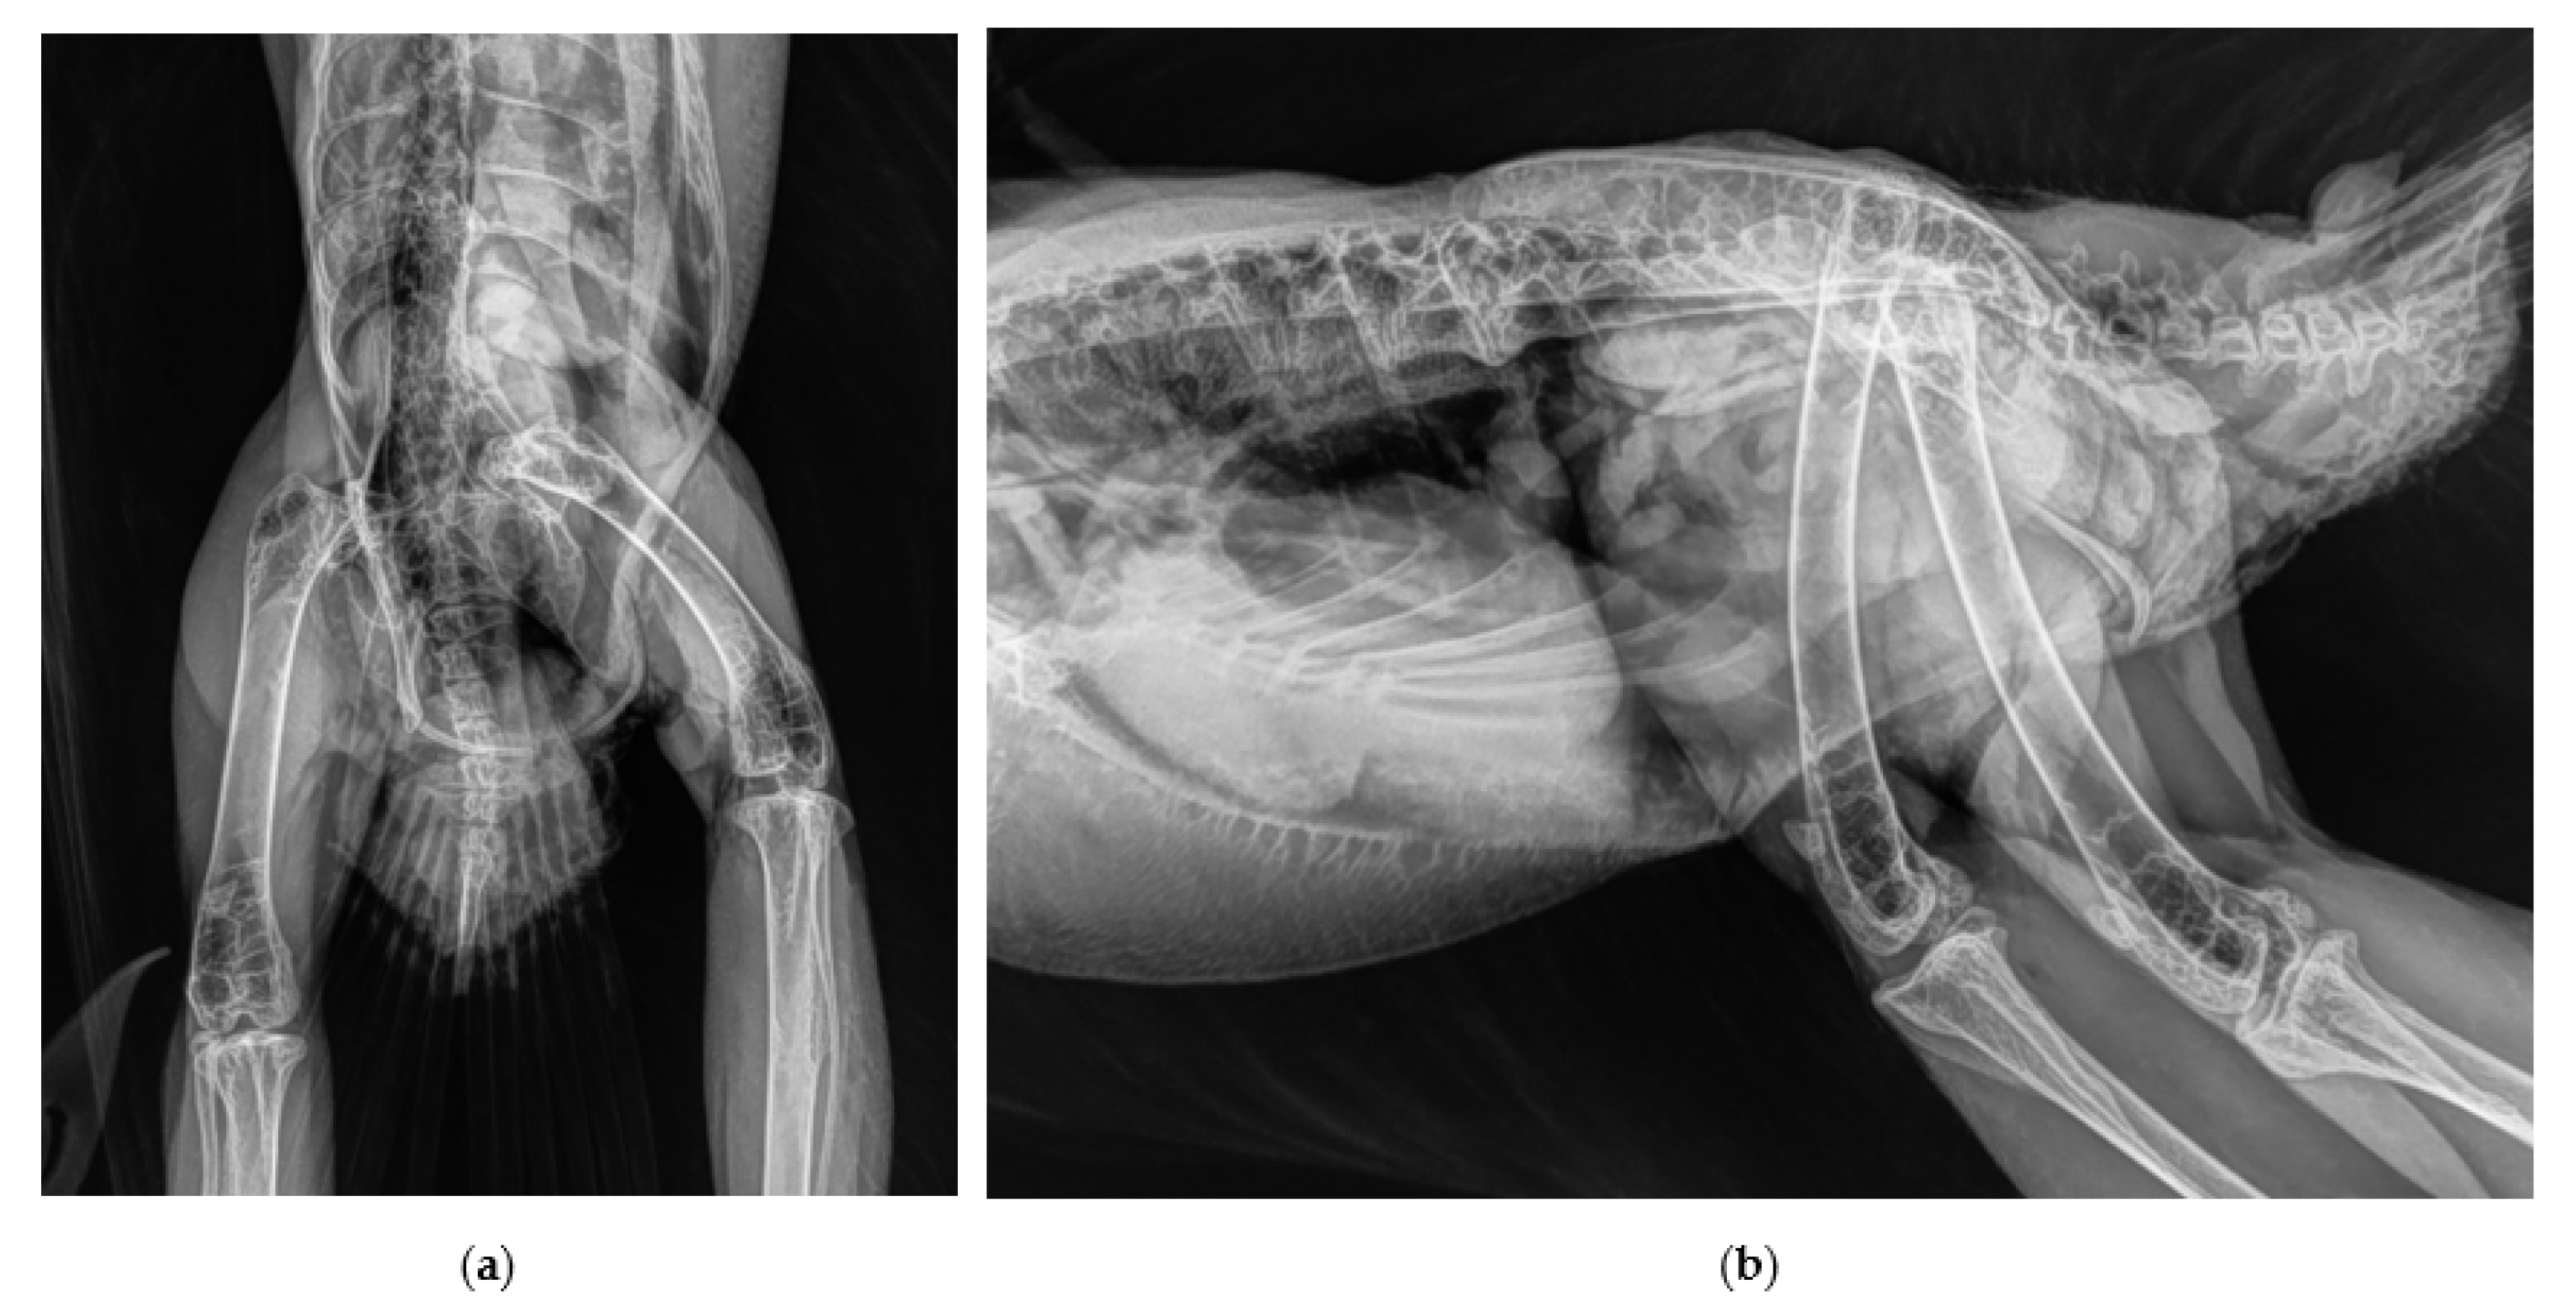

2.1. History and Clinical Examination

2.2. Surgical Procedure and Post-Surgery Management